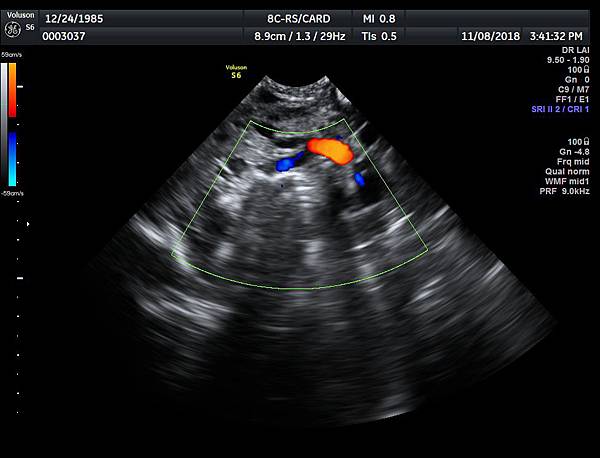

有一對夫妻因為我之前迷走性右側鎖骨下動脈(ARSA)的診斷而選擇孕兒診所,先生告知因為曾經有一個產前被我診斷ARSA的個案在他們醫院出生,他們花很久的時間才證實新生兒有ARSA,他覺得我很厲害,我有點不好意思,其實對專家而言,胎兒時期要診斷ARSA比新生兒容易,原因是胎兒時期超音波下,這條血管可以很清楚的被看到,它是從主動脈出來經過氣管的後面由左側繞到右側(附圖 1.),但是新生兒心臟超音波要看這條血管有困難,因為氣管擋住這條血管,醫師只能靠主動脈的第一個分支(brachiocephalic artery)沒有呈現 y 的特徵(附圖 2.),所謂 y 是brachiocephalic artery正常是會分出兩個分支(附圖 3.4.),一個是right common carotid artery,另一個是right subclavian artery,如果有迷走性右側鎖骨下動脈( ARSA ),就不會有正常的right subclavian artery,所以在新生兒的右頸部就不會看到 y的特徵,新生兒要直接看到迷走性右側鎖骨下動脈( ARSA)這條血管真的要花很多的時間(參考第51篇文章)。